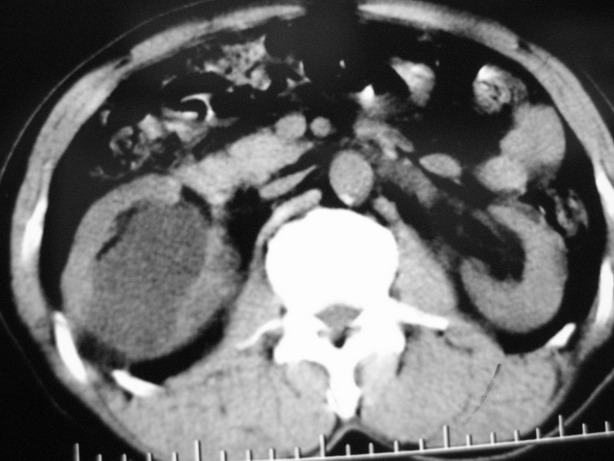

男性,48,体检发现,平时无症状。

收集期:

延迟期造影剂没有进入囊性病灶内考虑多发性肾囊肿,包括一个盂旁囊肿。

肾盂旁多囊性占位,有实性成分,增强有轻度强化,收集期病变内无造影剂显影。诊断肾盂旁囊肿,有实性成分无法解释,查书后诊断为:多房性囊性肾瘤!!不知大家同意否?????????对本病知道不多,望大家不吝赐教!!

囊间间隔强化与肾实质相仿,还是支持多发囊肿,定期复查